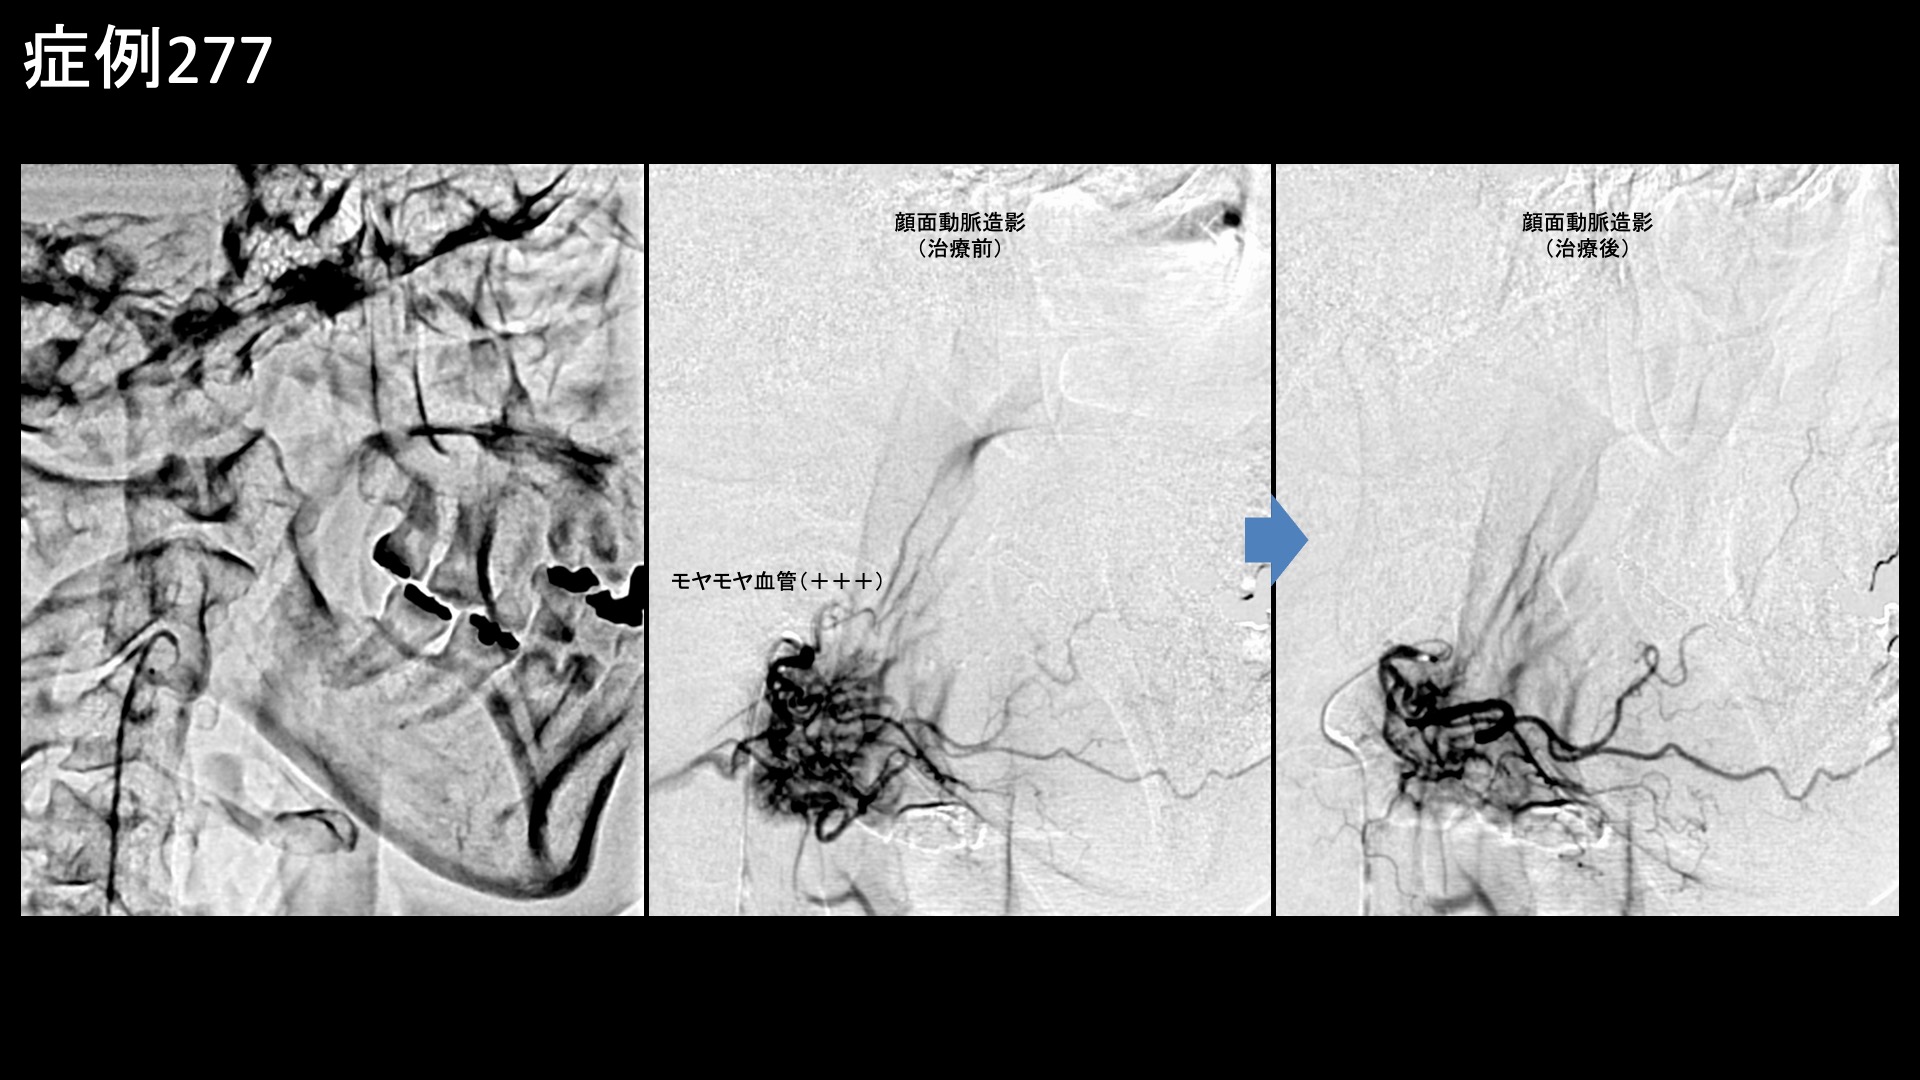

顔:頭痛など 【60代:女性】コロナ禍で急増した顎関節症(mask related TMD)はモヤモヤ血管治療で解決!顎関節症に対するカテーテル治療(顎関節症、コロナ禍、mask related TMD) 2026.04.07 鴨井院長による動画解説 受診までの経過 1年8ヶ月前から、朝起きたときに顎のズレを感じるようになりました。次第に、顎関節を中心として右耳の前方から下顎、さらには首肩まで痛むようになりました。痛みは起床後から寝るまで四六時中続き、歯科でマウスピース治療を受けましたが、治りませんでした。当院の治療を知り受診されました。 診察時の所見 首肩こりは元々なく、首肩の痛みはあくまでも顎関節症から波及しているとのことでした。診察上も特に問題ありませんでしたので、治療は顎関節のみに行うこととしました。顎関節症はモヤモヤ血管治療の適応疾患ですので、モヤモヤ血管(病的新生血管)に対する運動器カテーテル治療(微細動脈塞栓術)を受けていただきました。 治療の所見 顎関節に直接関係はしないものの、関連する筋・筋膜性疼痛を引き起こすため顔面動脈の治療は必ず行います。顔面動脈はモヤモヤ血管がよく描出される血管の一つです。血管造影を行うと、モヤモヤ血管が濃染像として豊富に描出されました。治療後は画像上速やかに消失しました。顎動脈でも、一定のモヤモヤ血管が同様に描出されました。治療時にはそれぞれ再現痛も確認できました。その他複数個所の治療を行い終了しました。 *再現痛とは、薬液投与時に普段の痛みが一定程度再現される現象です。責任血管の同定のための参考とします。 治療前画像:損傷を受ける、あるいは繰り返しのストレスにより発生した異常な新生血管 治療後画像:カテーテルを用いて塞栓物質を血管内に投与し新生血管を塞いだ状態 治療費用:治療する部位によって費用が異なりますのでこちらをご参照ください。 主なリスク・副作用等:針を刺した場所が出血により腫れや痛みを生じたり、感染したりすることがあります(穿刺部合併症)。造影剤によるアレルギー(皮膚のかゆみ・赤み・息苦しくなるなどの症状)が出ることがあります。 治療後の経過 治療直後から症状が改善しました。治療後1ヶ月の再診時には痛みが消失し、圧痛も無くなっていました。非常に経過良好であり終診となりました。 顎関節症はモヤモヤ血管が深く関わっている代表的な疾患の一つであり、治療後は他疾患よりも比較的早期から改善することが多いです。顎関節症はマスク生活により増加したと指摘されており、mask related TMDという言葉があるほどです。マスク関連性のTMD ;Temporomandibular Joint Disorder、顎関節症ということです。顎関節症にとっては、上下の歯列が接触する機会が増えることが最大の増悪因子なのですが、マスク生活ではまさにそうなるからです。ひどくなると、頭痛や首肩こりの原因にもなります。モヤモヤ血管治療の良い適応疾患ですので、お悩みの方はご検討いただくと良いかと思います。 顎関節症の詳細はこちら 【60代:女性】肩の激痛も石も消滅!石灰沈着性腱板炎に対する運動器カテーテル治療(石灰沈着性腱板炎、肩関節周囲炎) 前の記事